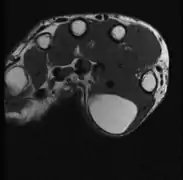

A physical exam is typically the easiest way to diagnose it. Rarely, a tissue biopsy or imaging may be required. The imaging modality of choice is magnetic resonance imaging (MRI), because it has superior sensitivity of distinguishing it from liposarcoma as well as mapping the surrounding anatomy.[20]

- MRI showing lipoma of the arm